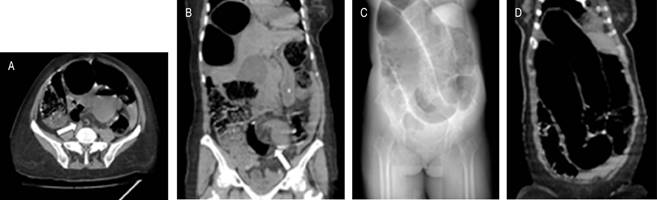

En la radiografía simple, la clave diagnóstica para el vólvulo sigmoideo es el colon dilatado sin haustras, con forma de “U” invertida y localizado en la línea media con dirección hacia los cuadrantes superiores. El signo del “grano de café” se produce debido a la imagen central creada por el contacto de las paredes mediales del asa volvulada y las paredes laterales que dan lugar a los bordes del grano (Figura 1).3 Sin embargo, sólo el 60% de los pacientes se logra diagnosticar mediante radiografía abdominal. La presencia de neumatosis lineal sugiere perforación inminente por necrosis intestinal; la presencia de aire libre sugiere perforación intestinal.11

Figura 1: Tomografía axial computarizada simple en la cual se evidencia signo característico del vólvulo sigmoideo de “imagen de whirlpool” (flecha) en corte axial (A) y coronal (B). Se evidencia signo característico de vólvulo sigmoideo en “grano de café” (C y D).

El estudio de elección es la tomografía computarizada debido a su sensibilidad de 100% y especificidad > 90%, debido a que permite crear reconstrucciones multiplanares que facilitan el diagnóstico definitivo.1 Los hallazgos son superiores a los de la radiografía simple; los signos específicos tanto de la tomografía como de la radiografía para vólvulos sigmoideo y colónico se muestran en la Tabla 2.3,11 No obstante, hasta 25% de los pacientes no presentaron estos signos característicos (Figura 1).